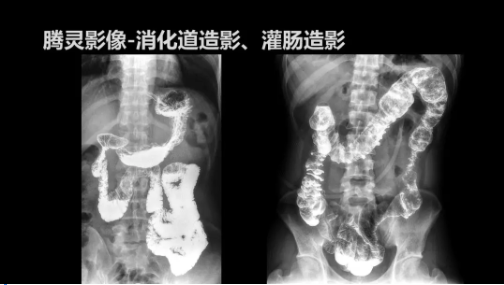

“騰靈”是安健科技的第四代動(dòng)態(tài)DR產(chǎn)品,可實(shí)現(xiàn)全科室應(yīng)用。如各類(lèi)常規(guī)的X線(xiàn)檢查、消化道檢查、骨科檢查、婦科、兒科檢查等。此外,安健科技為“騰靈”在真正意義上實(shí)現(xiàn)多科室、多功能診斷進(jìn)行了多項(xiàng)針對(duì)性設(shè)計(jì)。

相較前代產(chǎn)品,“騰靈”在圖像質(zhì)量方面得到了全面升級(jí),“騰靈”采用17*17非晶硅平板探測(cè)器設(shè)計(jì),采集矩陣達(dá)3072*3072,動(dòng)態(tài)范圍達(dá)16bit,為成像提供超大視野的同時(shí)保證成像質(zhì)量,此外,該款機(jī)型可根據(jù)醫(yī)療機(jī)構(gòu)的差異化需求而選配不同的動(dòng)態(tài)平板探測(cè)器,以此來(lái)適應(yīng)不同階層用戶(hù)所需。

此外,“騰靈”為了能夠幫助醫(yī)生更快速、有效的定位病灶,還增加了多項(xiàng)精準(zhǔn)診斷保障功能,如支持動(dòng)態(tài)觀察診斷,實(shí)時(shí)高清點(diǎn)片等?!膀v靈”透視切換高清點(diǎn)片曝光,捕捉關(guān)鍵病灶診斷僅需0.8s,同時(shí)還支持圖像局部放大,醫(yī)生可自由切換15’12’和9’三種放大模式,另外,“騰靈”還支持視頻保存、回放功能,幫助醫(yī)生在檢查結(jié)束后通過(guò)回放查看細(xì)節(jié),為醫(yī)生的診斷增加信心。